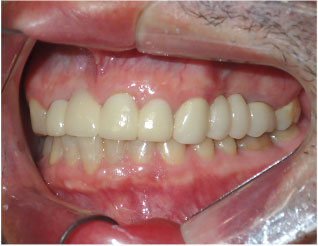

- ブリッジ 症例写真 B-0113FZC8本 女性モニターの方です。

Before

After詳細はコチラ

フルジルコニアによるブリッジ治療の症例

施術 FZC8本 - コメント

この方は古い差し歯の黄ばみを治したいとご来院されました。 奥歯に欠損もありましたので、前歯はジルコニアセラミック、奥はジルコニアブリッジで治しました。 1回の治療で前歯も奥歯も同時進行で治療します。 1回目の治療時に仮歯を入れますので、すぐに見た目が気にならなくなります。 治療回数は5回でした。